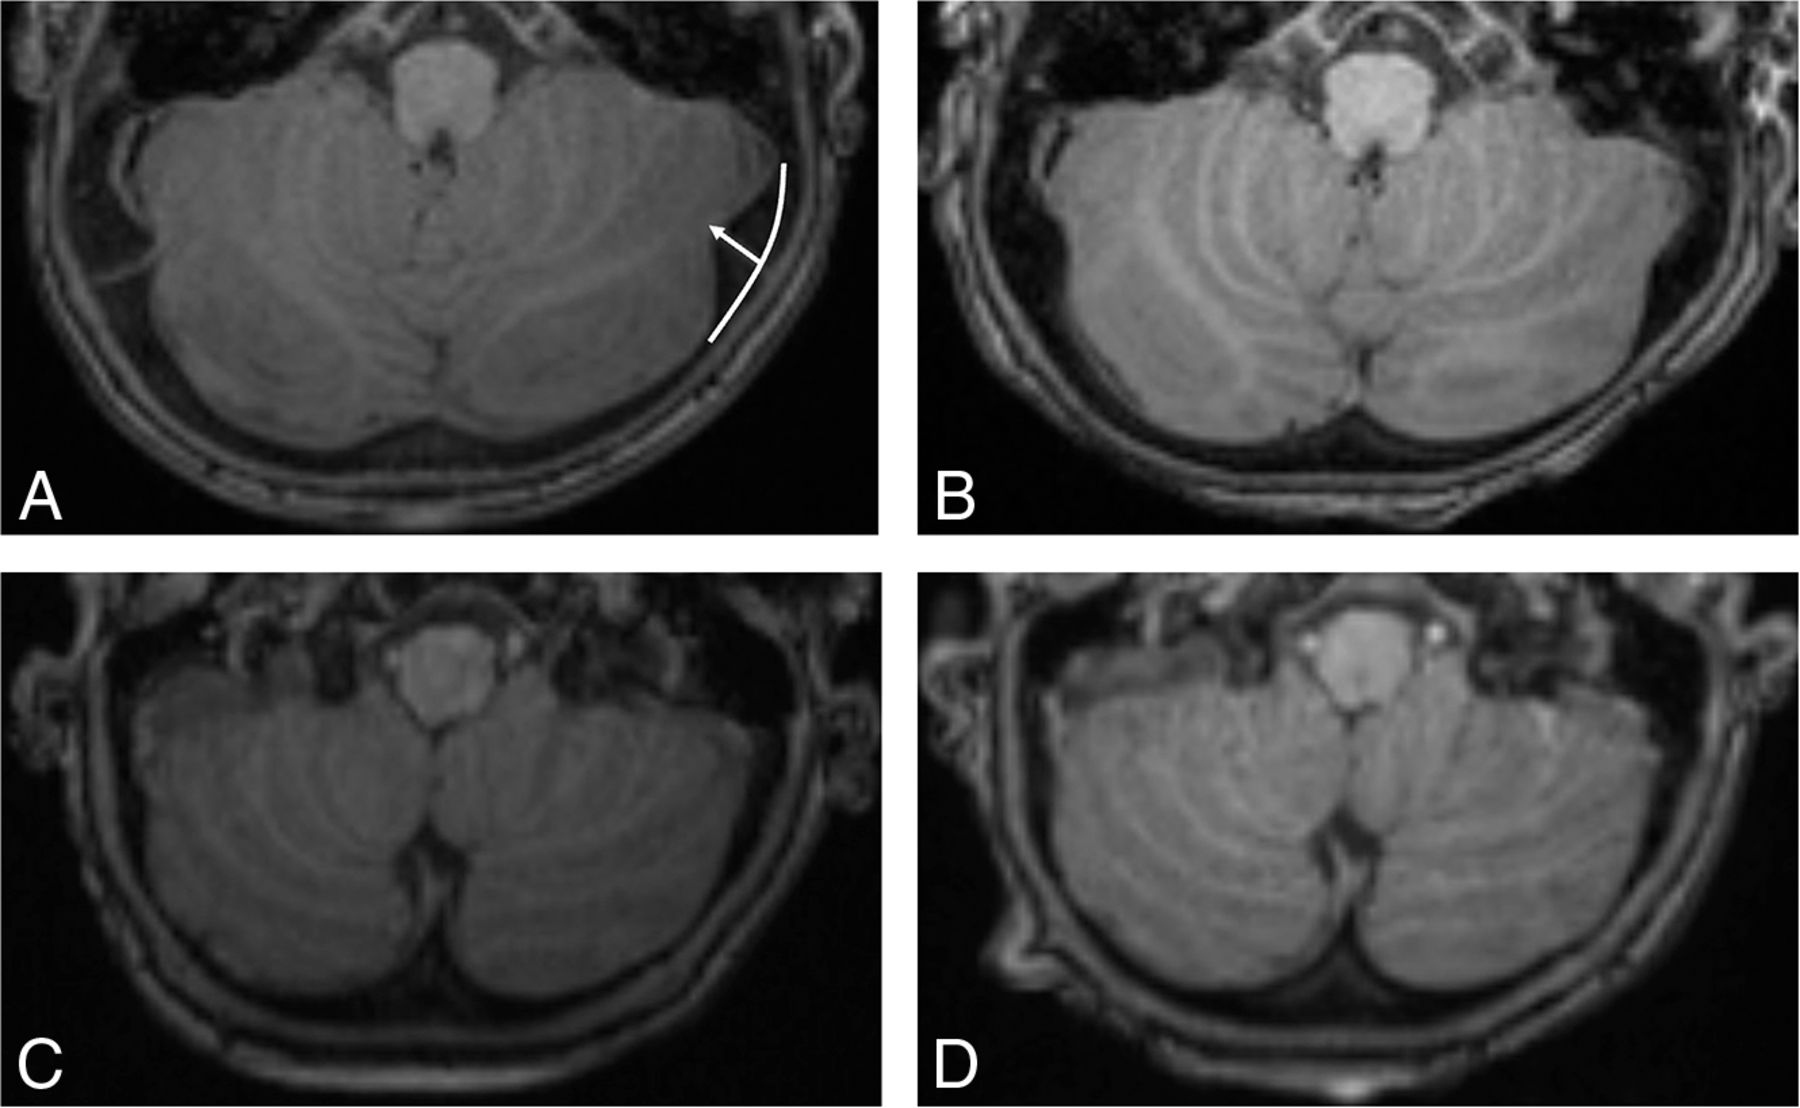

All patients with MPS IH treated at our institution between 1996 and 2015 were retrospectively reviewed. Each brain MR imaging of all patients during this period was reviewed. Axial reconstructions from 0.9-mm MPRAGE T1-weighted or axial 4-mm T2-weighted TSE images were used for measurement. When present, both the left and right posterior fossa horns were measured as the perpendicular distance from the tip of the horn to the expected curvature of the inner table of the occipital bone (Fig 1A). Consensus reviews were achieved among a medical student, a radiology resident, and a staff neuroradiologist. Basic linear regression was used to detect relationships between the changes of posterior fossa horns and age. Summary statistics and the Student t test were used to describe the averages of the posterior fossa horns.

A, T1-weighted axial images demonstrate a progressive decrease in the size of the posterior fossa horns in a patient who underwent hematopoietic stem cell transplantation at 1 year of age. The height of the posterior fossa horn is measured from the expected curvature of the inner table (curved white line) to the tip of the horn (A, white arrow). The posterior horns measure 6.3 mm R/5.4 mm L at 0.9 years (A). They are 4.1 mm R/3.2 mm L at 1.8 years (B) and 2.0 mm R/1.0 mm L at 4.1 years (C). D, They are 0 mm R/0 mm L at 5.9 years (D).